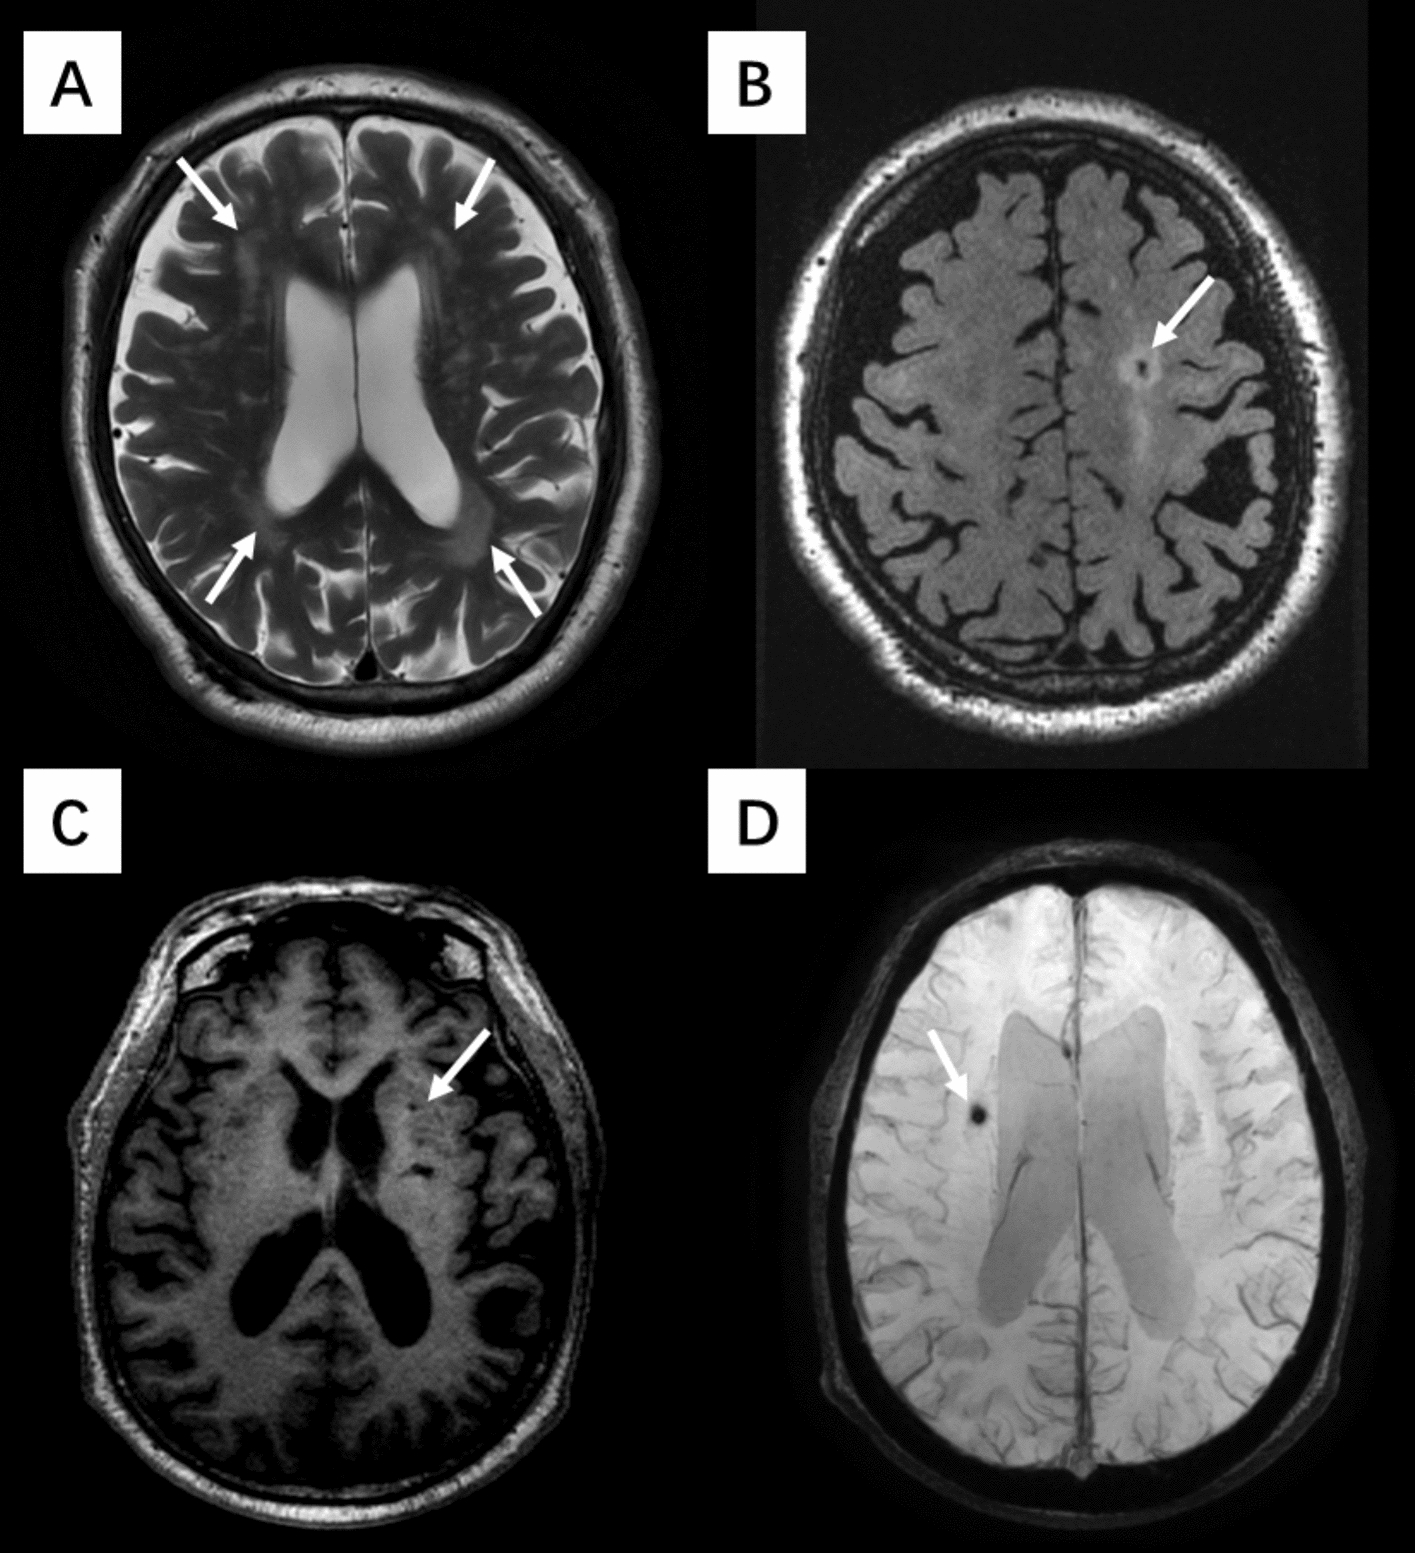

Methods: A total of 654 participants from the Kailuan community were included after those with incomplete data or carotid stenosis ≥ 50% were excluded. Carotid ultrasound was used to measure the peak carotid flow velocity (PSV), end-diastolic velocity (EDV), resistance index (RI), pulsatility index (PI) and carotid intima-media thickness (IMT) of the common carotid artery (CCA) and internal carotid artery (ICA). MRI was performed to assess cerebral perfusion and CSVD features, including white matter hyperintensities (WMH), lacunes (LA), cerebral microbleeds (CMB), and enlarged perivascular spaces (EPVS). Multivariate regression models were used to analyze the associations of carotid hemodynamics with cerebral perfusion and CSVD.

Results: CCA-EDV was positively associated with whole-brain perfusion (β = 0.14, p = 0.017) and regional perfusion in gray matter (GM) (β = 0.16, p = 0.012), frontal (β = 0.15, p = 0.014), parietal (β = 0.19, p = 0.006), temporal (β = 0.14, p = 0.020), and hippocampus (β = 0.12, p = 0.034), but no significant associations were found between CCA-EDV and white matter (WM) perfusion. A higher CCA-EDV was associated with a lower risk of LA (OR = 0.93, p = 0.029). The CCA-PSV was negatively correlated with the total CSVD score (OR = 0.99, p = 0.047). No significant associations were detected between other carotid hemodynamic parameters and LA, CMB, EPVS, WMH, or total CSVD score.